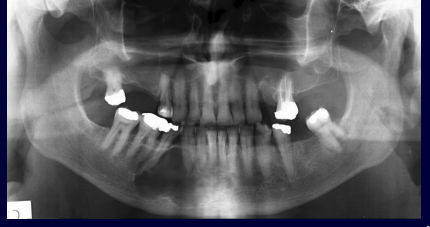

What is the common appearance of the radicular cyst?

Lesion consists of a lucent centre and a thin, well-defined sclerotic rim. Cortical bone destruction may occur if cyst becomes too big.

Q

Lesion uniformly lucent with a thin, well-defined sclerotic rim attached to the cemento-enamel junction.

Odontogenic keratocyst is a well-defined sclerotic which causes less jaw expansion and grows along the jaw bone.

Has aggressive growth characteristics. Typically well-defined and radiolucent. Cause root resorption, tooth displacement and bone expansion. Floating tooth appearance.